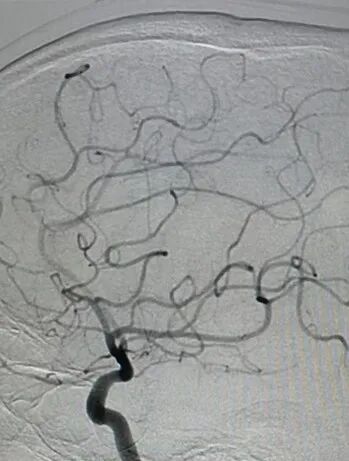

术后影像及检查

术后正位造影。

术后侧位造影